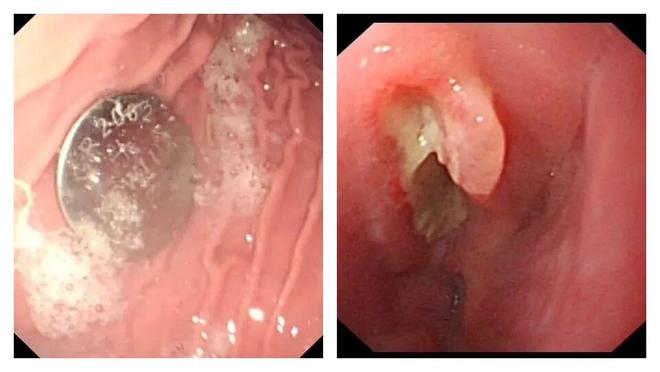

家长们注意!幼儿误吞纽扣电池10小时食道被腐蚀穿孔

近日,江苏南京市儿童医院公布了一起令人痛心的案例。今年5月,江苏南京1岁半的宁宁(化名)突然出现呕吐、拒绝进食的情况,随后家长发现玩具中的纽扣电池不见了,才意识到孩子可能误吞电池,立即将其送往医院。

医生利用胃镜取出了卡在食道的电池,但距离孩子吞下电池已经过去10个小时,孩子的食道被电池释放的化学物质腐蚀并穿孔。

南京市儿童医院消化科副主任医师练敏介绍,电池取出两周后,造影发现宁宁被灼伤的食道因瘢痕形成狭窄,导致吞咽困难,落下终身残疾。后续医院又多次对宁宁进行食道扩张治疗,尽可能恢复食道功能。

纽扣电池被误吞卡在食道后,就像启动了一个 “微型电烙铁” 。 电池正负极会通过湿润的人体组织形成电流,并泄漏强碱性液体 ,造成 化学烧伤、电烧伤 等多重打击。

通常来说,灼伤在电池吞入后15-30分钟内就开始发生,超过6小时就可能导致食道严重烧伤、穿孔,甚至永久性损伤,或导致终生无法正常进食。